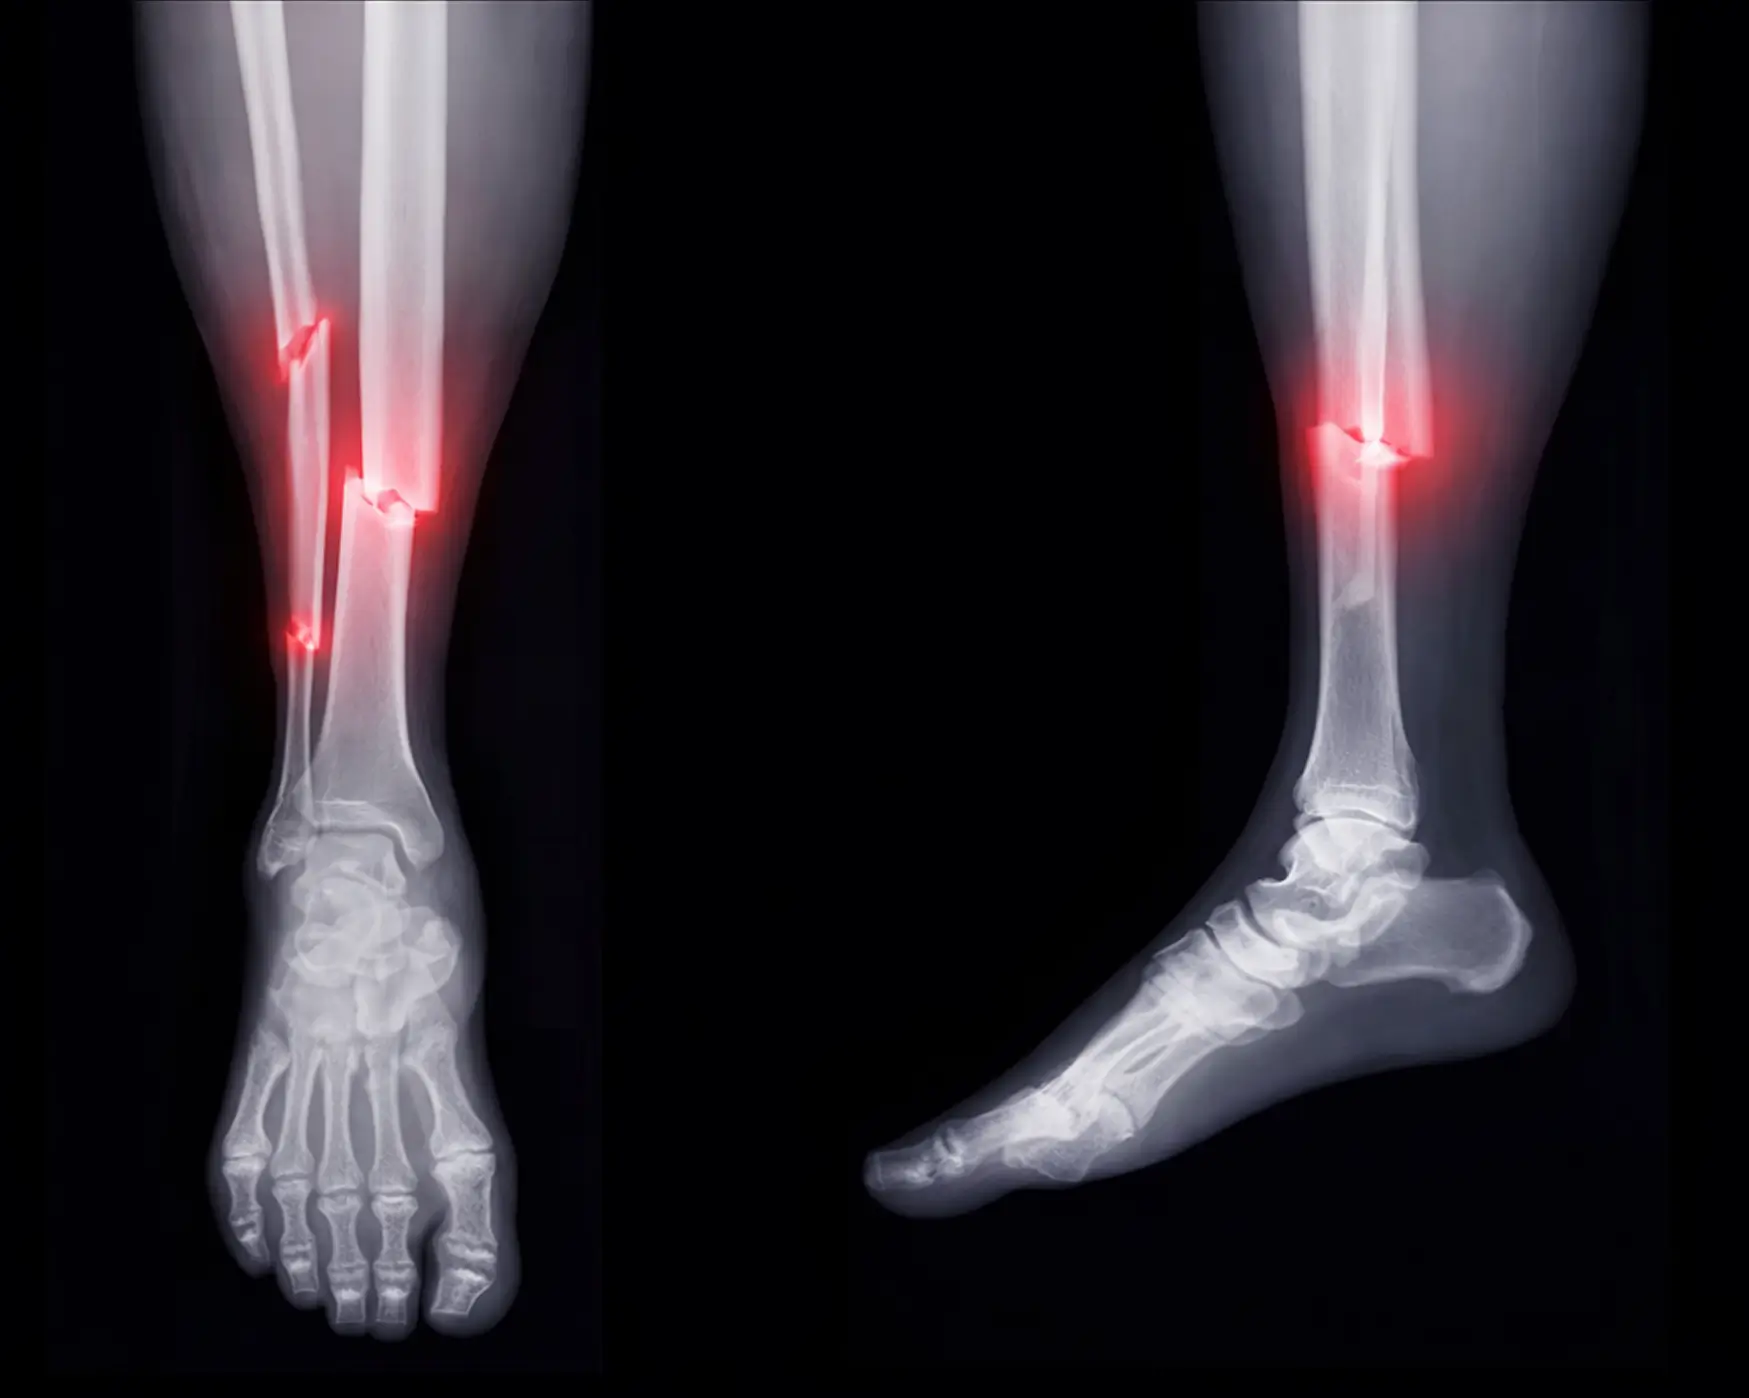

The Complexity of Bone Fractures

Bone fractures are more than just breaks in the bone; they are intricate injuries that can significantly impact one’s mobility & quality of life. The nature of a bone fracture varies, ranging from simple cracks to breaks, & the treatment approach must be tailored to each individual case.